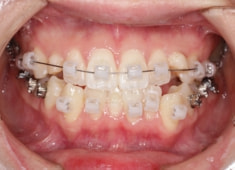

治療開始時